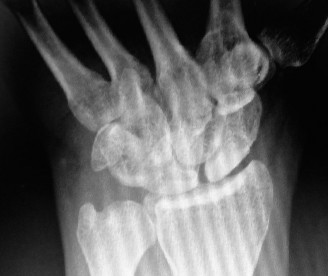

CASE 27 ### Several years after sustaining an injury to his wrist, a firefighter presents to your clinic with chronic wrist pain. What does his x-ray (Fig. 3–20) reveal?

Figure 3–20(©) Sunil Thirkannad and Christine M. Kleinert.

The correct answer is (C).

The correct answer is (D). Ulnar translation of the lunate indicates weakness of the radio-scaphocapitate ligament. This serves as a relative contraindication for proximal row carpectomy as the risk of the capitate also translating ulnar wards is high, leading to an unstable wrist.